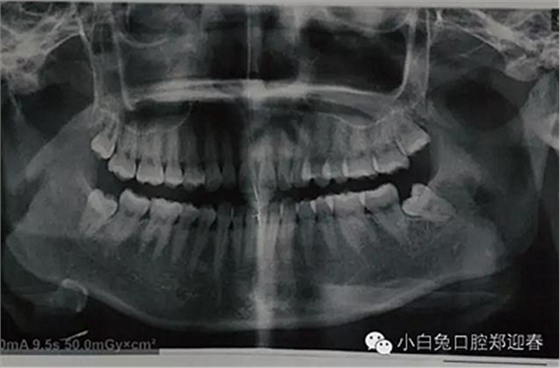

患者19歲,四顆智齒,日前,專門從西安趕過(guò)來(lái)要求智齒拔除,檢查發(fā)現(xiàn),18、38、48均未萌出,僅28萌出一頰尖,全口曲面顯示,38近中埋伏阻生,牙根瀕臨下頜神經(jīng)管,擬計(jì)劃,局麻下分兩次給予四顆智齒拔除。